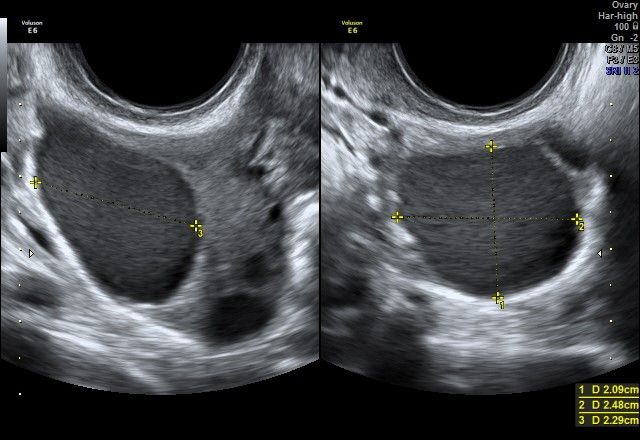

diagnostica ecografica tranvaginale con eco color doppler di I e II livello e transaddominale

Foto e video